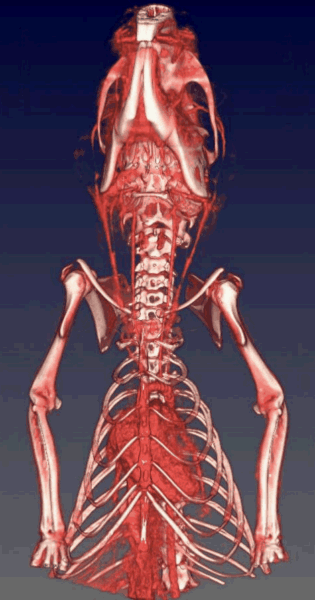

CASE 7: High workflow ex-vivo CT study of skeleton

workimg

• Courtesy of: S. Soussoko - Laetoli Productions / D. Brasse - IPHC CNRS Strasbourg

Research objective: Reconstitution of skeleton of Caribbean fruit bat

Animal model: Brachyphylla cavernarum. Dimensions: Skull length = 3 cm, Body length = 8.5 cm (incl. tail)

Acquisition protocol: 112 s acquisition time, 80 kVp, 1 mA, 1 bed position per plate, 6 acquisitions (complete skeleton), Total scan time < 12 min

Processing and reconstruction protocol: 0.06 mm isotropic voxel size